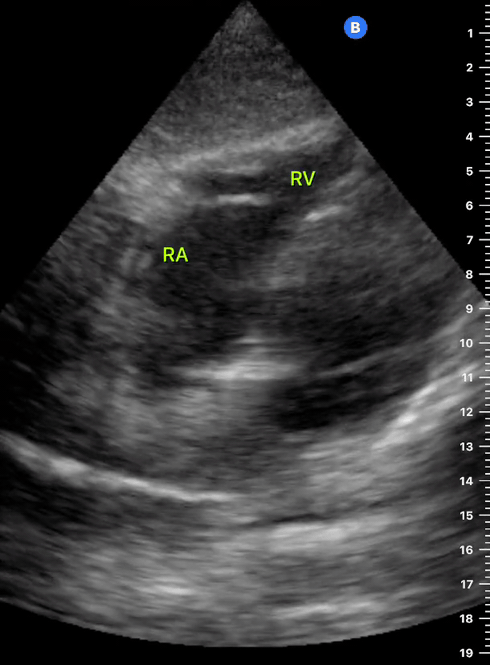

This is the standard window taught in FAST and might be the only one available during cardiopulmonary resuscitation (CPR). This view uses the liver as an acoustic window. To obtain good visualization is essential to handle the probe almost parallel to the anterior abdominal wall, trying to place it under the xiphoid process, pointing to the left shoulder. A deep inspiration or half inspiration can be useful to bring the heart closer to the probe and improve visualisation.

Remember that in the cardiac preset, the screen marking is on the right side. As a result, and unlike the FAST exam, the probe marking points towards the patient’s left. This view is used mainly to look for pericardial fluid, but it also provides information about ventricle size, chamber relationship and valvular abnormalities.